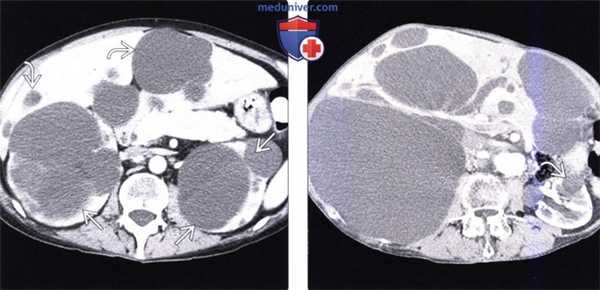

(Слева) На аксиальной КТ с контрастным усилением, выполненной женщине среднего возраста, определяются множественные кисты большого размера в поликистозно измененных почках и печени У женщин с поликистозной болезнью печени кисты обычно крупнее, чем у мужчин, что связано с влиянием гормонов на процесс развития кисты.

(Справа) На аксиальной КТ с контрастом у другого пациента определяются множественные кисты в печени, некоторые из которых имеют размер больше 20 см. В почках также определяются небольшие кисты. Правая почка смещена каудально, ее лоханка (не показана) сдавлена, что привело к гидронефрозу.